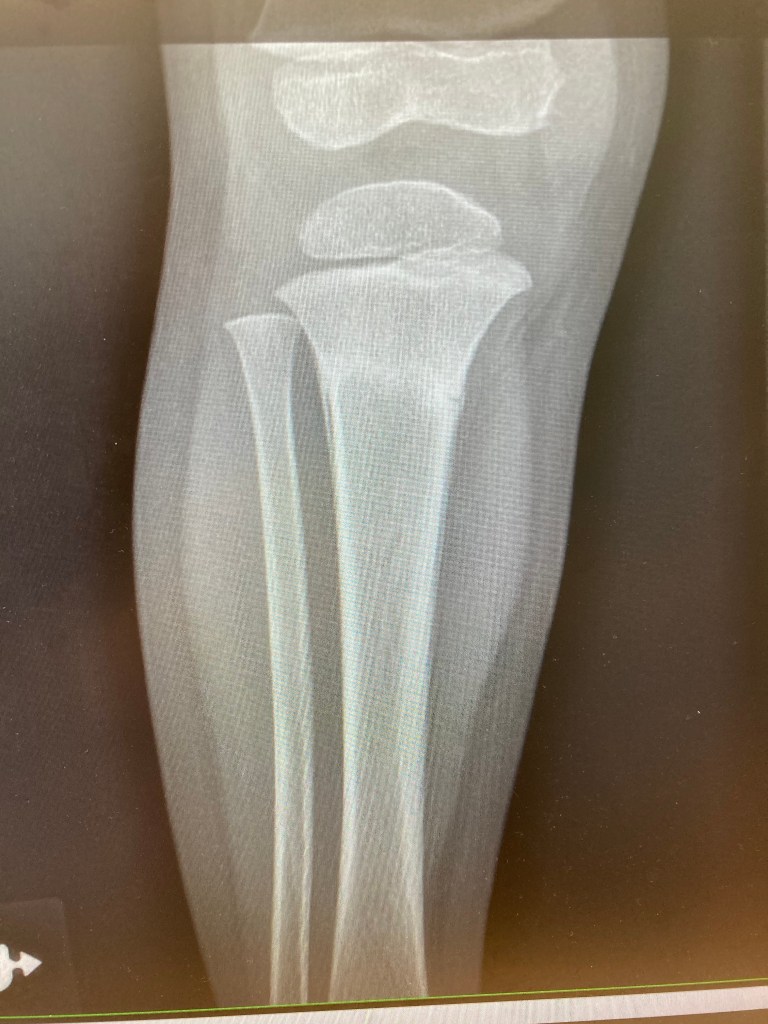

–Justus Broke his leg sledding.

My eyes followed, first and foremost, the course of his little cranium. Justus endured a fractured skull when he was 8 months old, so another could be fatal. The distance closed between him and the metal post of the fence, but his head was clear. His face did contact the chain-links, giving him a bloody lip, but nothing more. After I had raced to his side, his cries surfaced and his small voice indicated a total surprise: ”My leg hurts, dada!! My leg!!” I was shocked. No, it can’t be too serious. Didn’t he miss the pole completely? I looked down to his leg and his boot looked like it had been almost flung off his foot. Was this like that before? I took the boot off to check that everything was in tact, then touched a couple spots to see where it hurt the most. After getting a better sense for his pain level (difficult to determine with little ones), I breathed warm air on his exposed leg and carried him home.

This was a Saturday night around 6pm. We returned home and talked with Katie about the accident while taking off Justus’ snow clothes. What should we do? We were slightly skeptical that it was a broken bone, but there were a few needs to be met before making the decision to pursue urgent care. We set our wounded warrior on the couch and turned on some Charlie Brown to distract him from the pain. He was in a daze as we brought him dinner and ice packs. We asked him a few questions about the leg, but only after a little while came the true test. He had just effectively become potty trained a few months prior and he was now asking to go to the bathroom. Katie and I exchanged looks and I said the words, preparing myself to catch him. ”Okay, go ahead.” But it only took one step for him to fall to the ground in tears. I embraced him and brought him to the bathroom while Katie called the Urgent Care that was closing soon. We got ready, Justus and I (Katie needed to stay with the baby), and went to the doctor. He was such a good sport through the whole process, though we could only secure a wrap until Monday, when we would drive to a pediatric specialist for a kid’s cast. Justus chose orange. And the doctors gave us a boot to strap on for him to walk around, which he was doing within the hour, hah!

A few blessings along the way: 1. He didn’t hit his head. 2. The Urgent Care hadn’t closed yet, that Saturday night, though we almost missed them. 3. We still had our really good insurance from when Katie was a teacher. 4. Several church families came to support us with meals and company. 5. Justus was a champ and healed in 5 weeks!